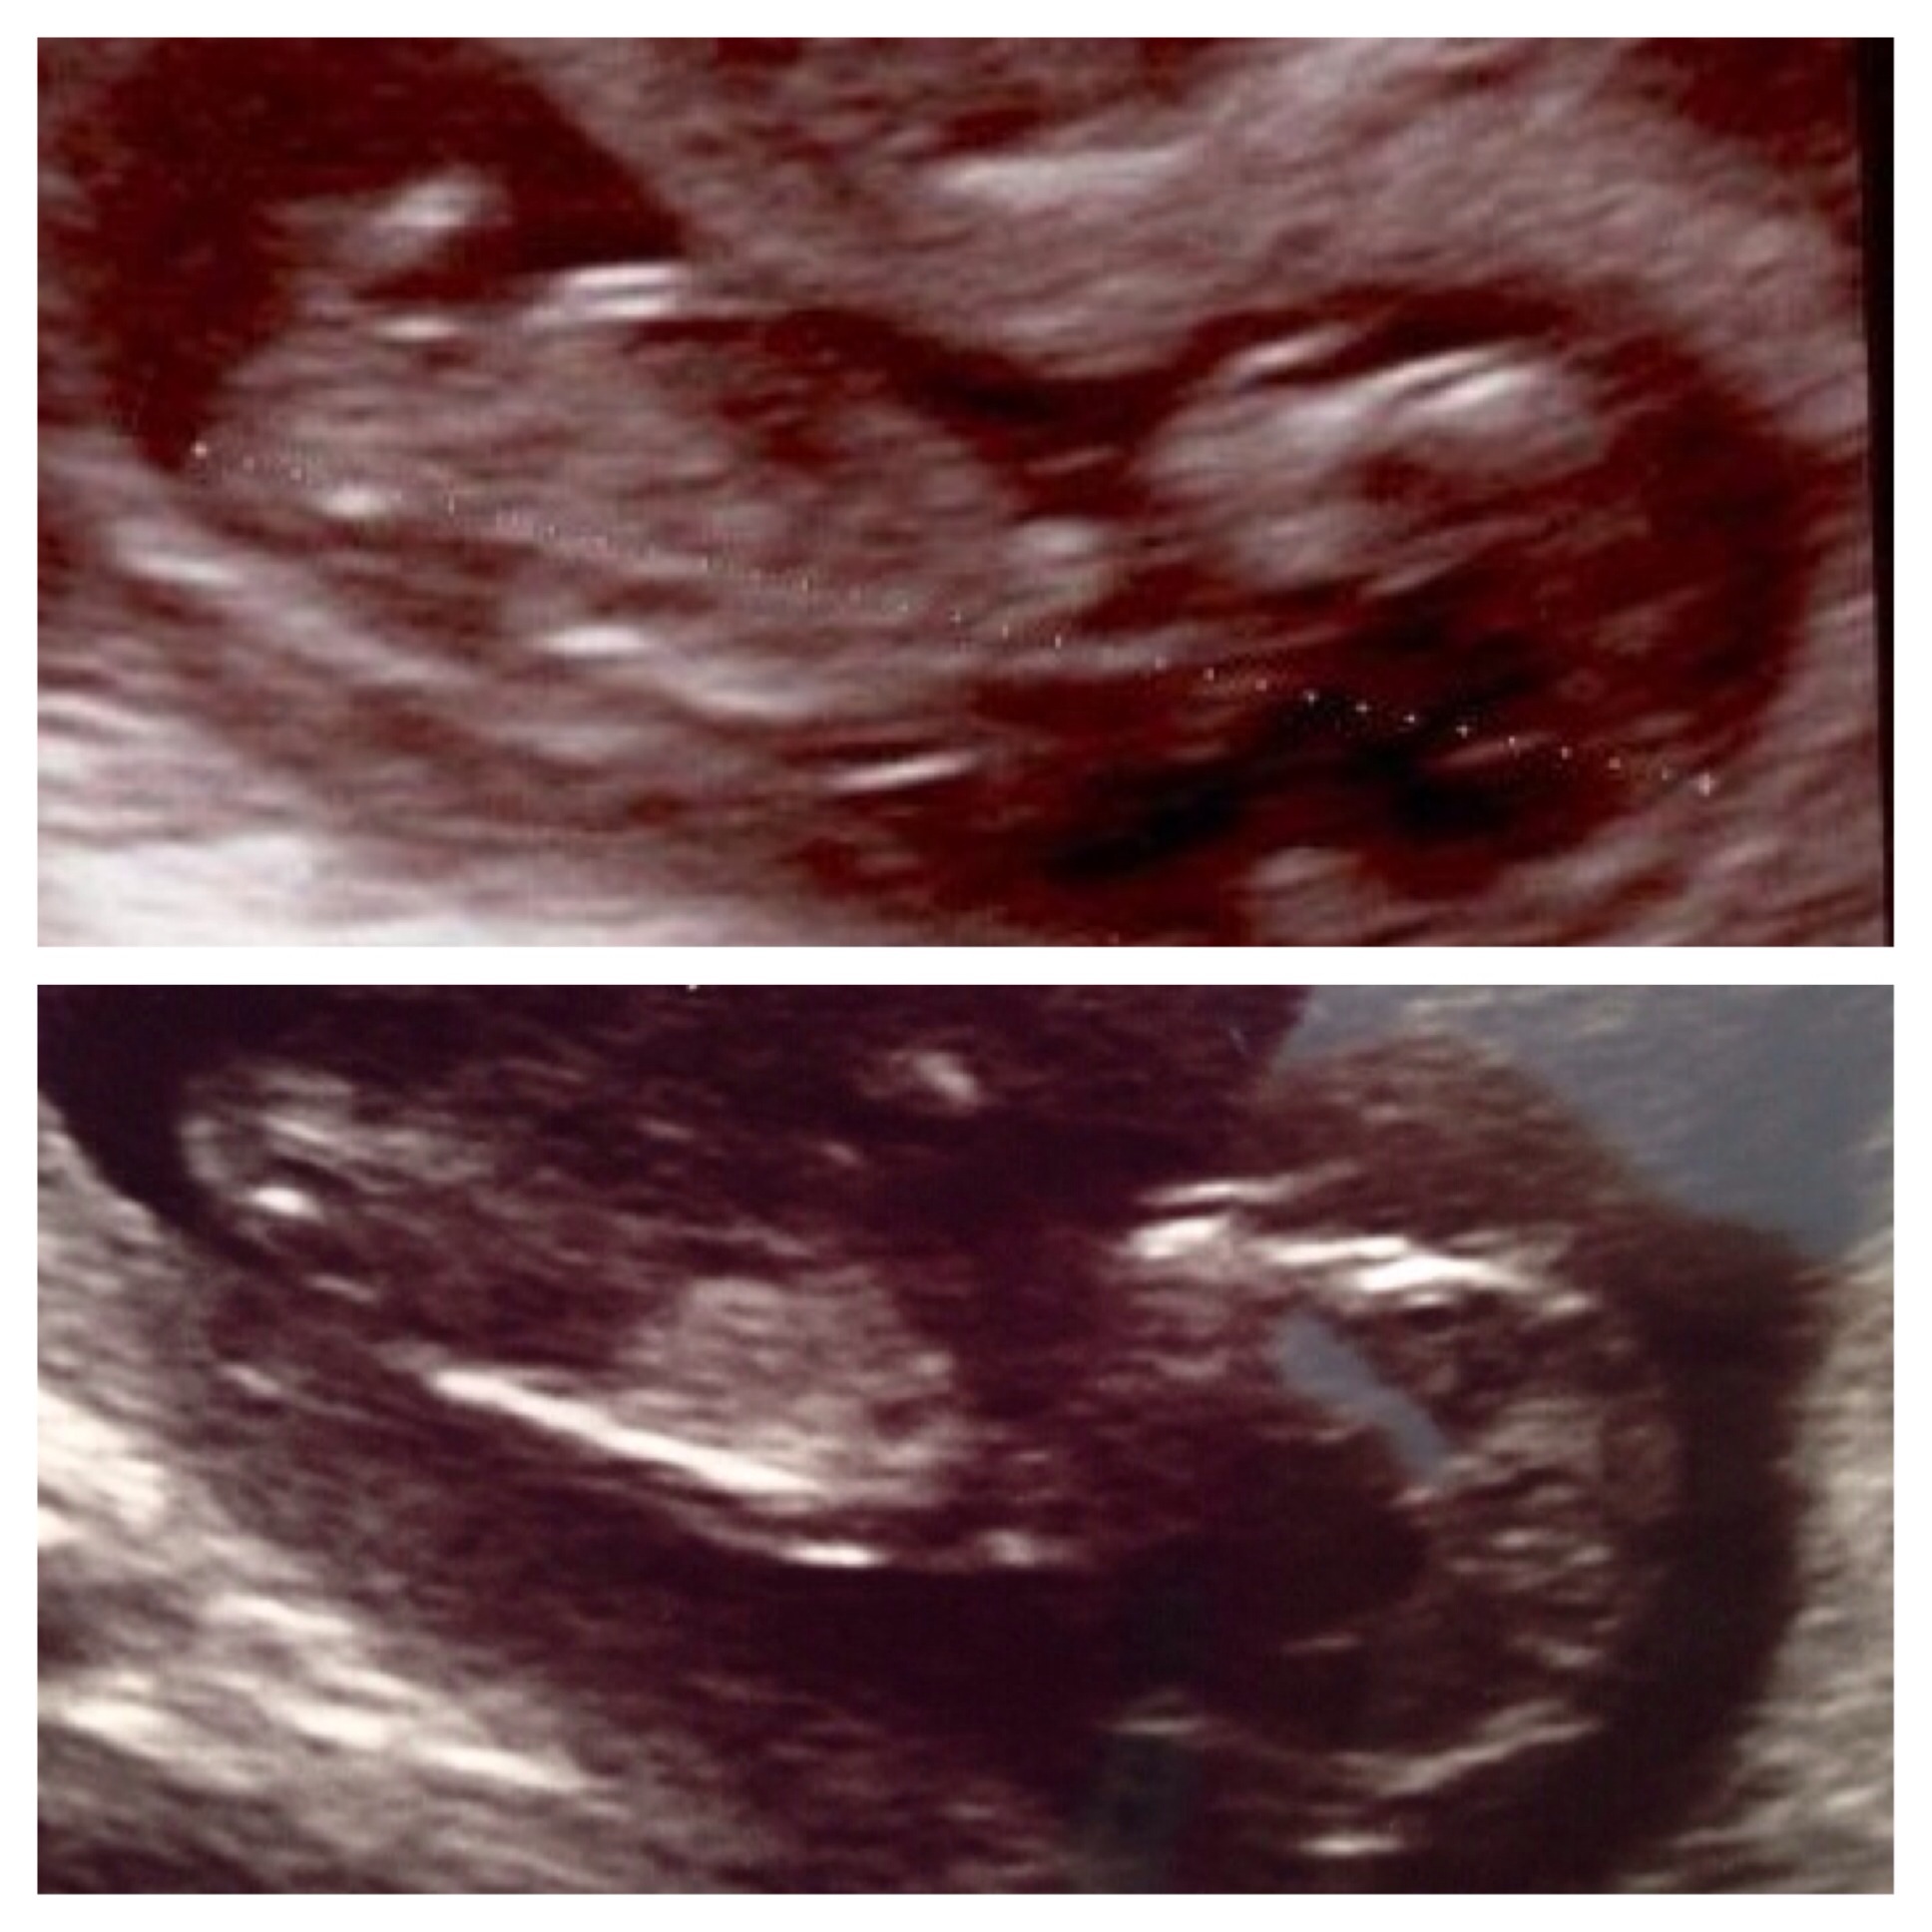

Attachment 18389Attachment 18390Attachment 18391

The one with he two babies: top baby is my 1st daughter and bottom baby is our 2nd little girl!

Other pics are of DD2!

It's another girl!!! JEEEEEEJJ!!!!

Confirmed at 15 weeks and 16 weeks and 18 weeks!